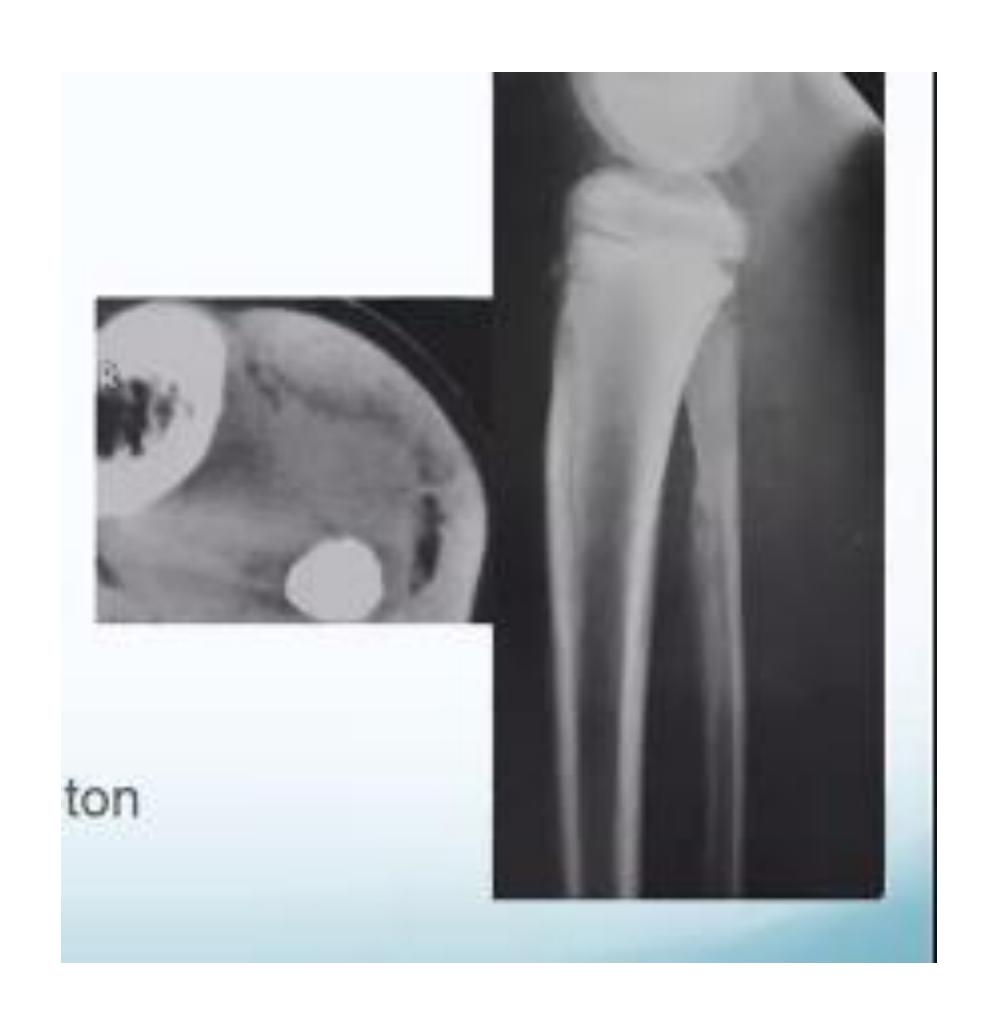

Tibia and Fibula Fracture

Diagnosis: Segmental and comminuted fracture of tibia and fibula

Tibial Plateau Fracture

Diagnosis: Tibial Plateau fracture Characteristics: Intra-articular Treatment: ORIF CT scan is necessary for evaluation